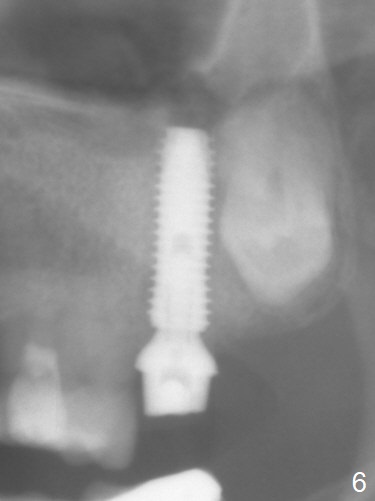

Extraction of the tooth #15 with short clinical crown (suggesting bruxism, Fig.1) reveals a vertical root fracture (Fig.2 <). It seems unnecessary and difficult to create osteotomy in the mesial slope. What can be done is to place starter and 2 mm drills as mesial as possible (Fig.3 (red dashed line: sinus floor). After use of Lindamann bur to move the osteotomy mesially and sequential osteotomy until 3.8x18 mm, a 4.5 mm tap is inserted with clearance from the impacted tooth #16 (Fig.4). A 5x15 mm implant is placed with >60 Ncm with clearance from the 3rd molar (Fig.5,6). If the impacted tooth were removed, the primary stability is expected to be reduced. Impression is taken 6 months postop with 19/20 implants (Fig.7). The bone graft remains in the crestal area immediately and 11 months post cementation (Fig.8,9 *). In the other word, new crestal bone forms after extraction.